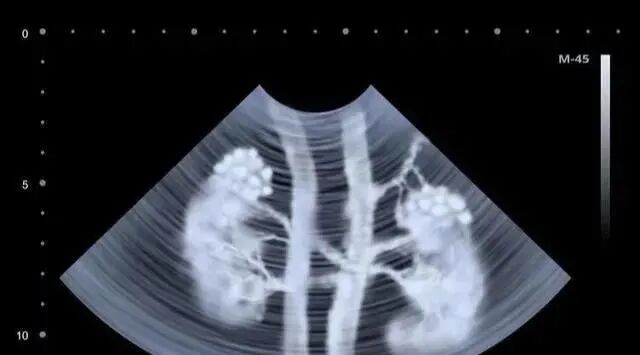

研究显示,静脉回输的MSCs能够迁移到急性和慢性肾损伤模型动物的肾小球、肾间质、小管周围血管和肾小管。